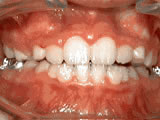

Crowding of the teeth

Before

AfterThis boy started treatment at age 11 and wore braces for 26 months. He loves his new smile.